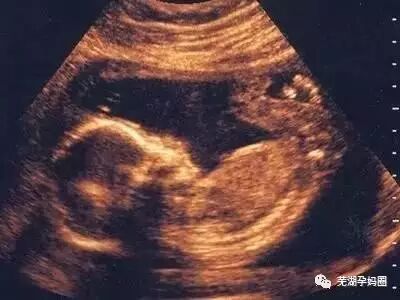

1. 男性胎儿会在母亲子宫里勃起

大多数妈妈都不喜欢讨论这个话题,但不少争论的事实是许多男婴在子宫里都会犯错。研讨发现,男女婴儿在子宫内都可能有手淫的举措,超声波图像也曾抓拍到男婴的勃起图片。不过只有男性能在X光片上看出来,原因嘛…你们懂的。